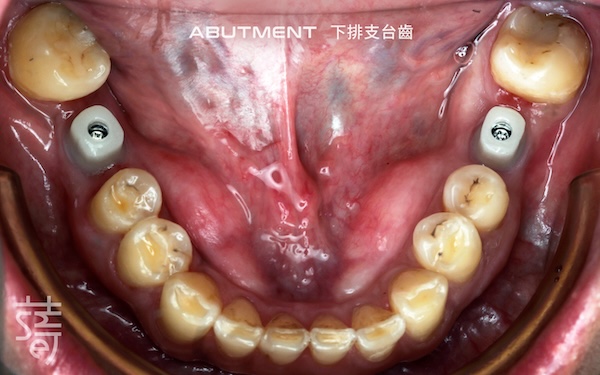

針對缺牙已久的後牙區進行植牙,恢復後牙支撐,避免整體咬合繼續崩塌,讓口腔受力更均衡。

Implants were placed in the long-missing molar areas to restore support, prevent further bite collapse, and balance oral forces.